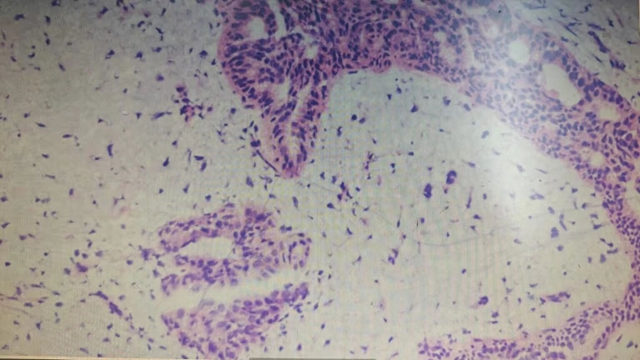

科室冷婕副教授接诊后,结合杨女士带来的彩超报告及查体结果,高度怀疑为乳腺肿瘤。为了明确性质,冷婕为杨女士进行了空芯针活检,病检结果提示:交界性分叶状肿瘤。

乳腺分叶状肿瘤是一种纤维上皮性乳腺肿瘤,占女性乳腺肿瘤的0.3%-1%,40-50岁女性为高发人群,男性罕见。

根据世界卫生组织(WHO)标准,它可分为三类:

良性分叶状肿瘤

交界性分叶状肿瘤(低度恶性)

恶性分叶状肿瘤(高度恶性)